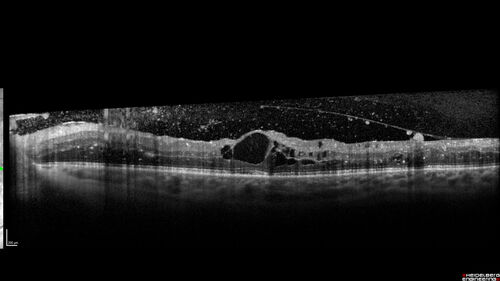

Proliferative Diabetic Retinopathy and vitreous hemorrhage left eye

44 year old man with type II diabetes for 14 years and no eye examinations in the last 5 years.  VA 20/40 right eye and 20/60 left eye.  Vision loss has been for about a week in the left eye.